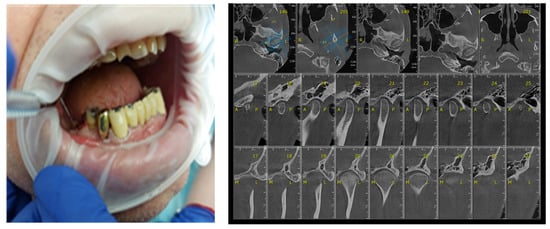

Certain factors increase the risk of periodontal disease: stress, smoking, heredity diabetes mellitus, poor oral hygiene, crooked teeth, underlying mmune-deficiencies, such as AIDS, fillings that have become defective, medications that cause dry mouth, bridges that no longer fit properly and female hormonal changes, such as with pregnancy or the use of oral contraceptives [29,30]. The participants’ gingival status was assessed using the WHO periodontal probe, measuring four gingival units (mesial, distal, vestibular, lingual) corresponding to each of those present in the oral cavity and observing whether or not bleeding was present (Figure 6).

Figure 6.

Correlation between Periodontal probing and TMJ exam. (a) Clinical aspects of periodontal damage; (b) TMJ changes related to periodontal status.